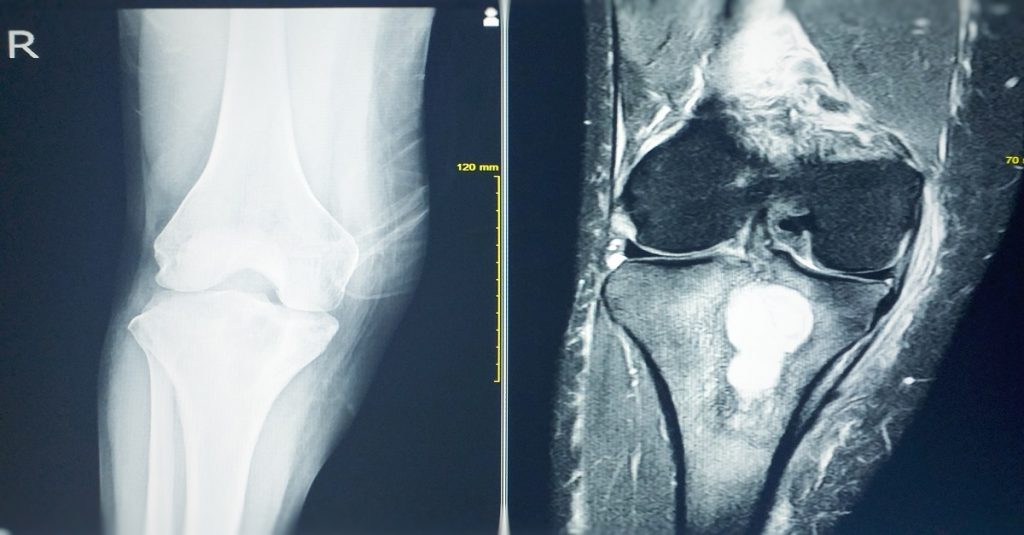

L’imagerie présente une place primordiale dans le diagnostic :

- Radiographie : ostéolyse.

- Scanner très détaillé dans la description osseuse pathologique.

- IRM plutôt utilisée pour les extensions dans les parties molles ou les compressions neurologiques.

L’IRM est actuellement l’examen de référence, permettant de caractériser plus précisément la tumeur, sa topographie et son extension éventuelle dans les parties molles.

La tomodensitométrie peut ainsi préciser les caractères de l’atteinte osseuse

L’ostéosarcome est la tumeur primitive la plus souvent en cause. Ainsi, il demeure localisée le plus souvent près du genou.

Les critères de malignité radiologiques restent généralement facilement mis en évidence et doivent faire adresser le jeune patient en milieu spécialisé où sera pratiqué un bilan d’extension par IRM sur l’os atteint.